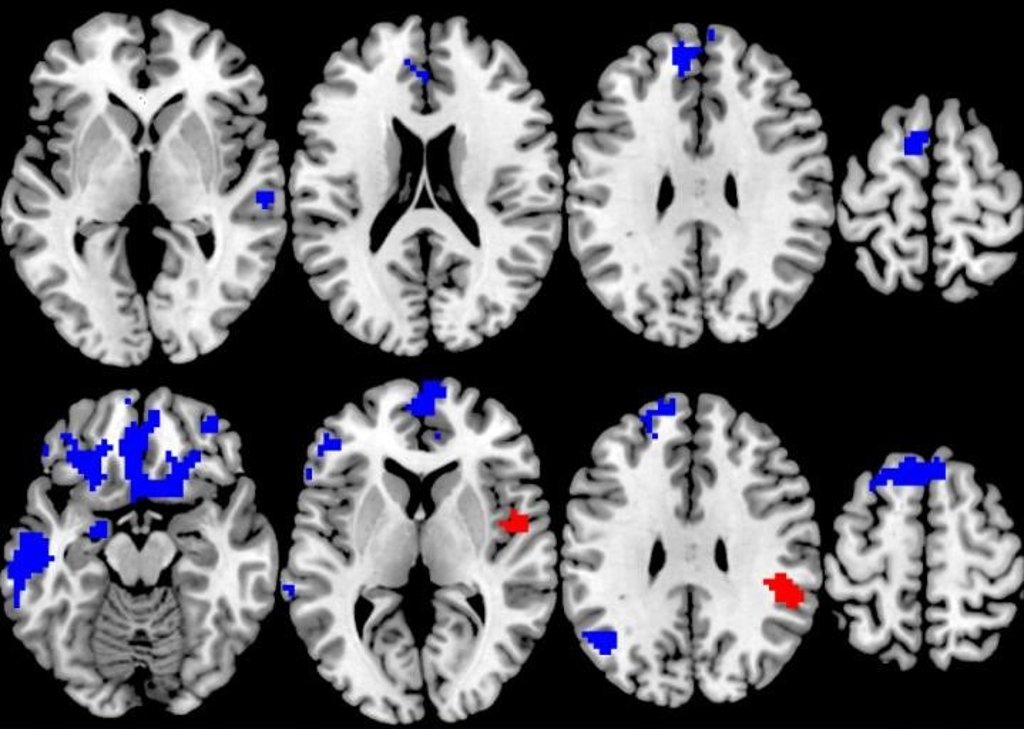

El nuevo estudio, publicado en la revista ‘American Journal of Psychiatry’, examina los escáneres cerebrales avanzados de 87 adolescentes y adultos con TOC de moderado a severo que fueron asignados al azar a 12 semanas de uno de los dos tipos de terapia.

Pero cuando los investigadores analizaron los escáneres cerebrales realizados antes de que los pacientes comenzaran la terapia y los relacionaron con la respuesta al tratamiento individual, encontraron patrones sorprendentes.

Los escáneres cerebrales se tomaron mientras los pacientes realizaban una simple tarea cognitiva y respondían a una pequeña recompensa monetaria si hacían la tarea correctamente.

Los que empezaron con más activación en los circuitos cerebrales para procesar las demandas cognitivas y la recompensa durante las pruebas tenían más probabilidades de responder a la TCC, pero los que empezaron con menos activación en esas mismas áreas durante las mismas pruebas tenían más probabilidades de responder bien a la TSM.

«Encontramos que la forma de terapia más específica para el TOC, la que se basa en la exposición al foco de la obsesión y la compulsión, era mejor para aliviar los síntomas, lo que en sí mismo es un valioso hallazgo de esta comparación aleatoria cara a cara de dos opciones de tratamiento. Pero cuando observamos el cerebro para ver qué había detrás de esa respuesta, encontramos que cuanto más fuerza tenían los pacientes en ciertas áreas del cerebro, más posibilidades había de responder a la TCC basada en la exposición», explica la líder del estudio, Stephan Taylor.